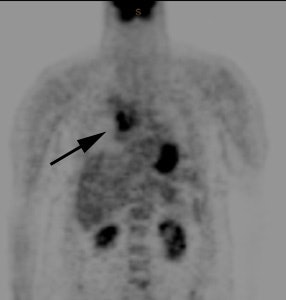

CT imaging confirmed a right upper lobe collapse with a central mass (white arrow). The lesion was hot on PET imaging (black arrow) and there was also uptake within pathologic mediastinal lymph nodes. The lesion proved to be a non-small cell lung cancer.  |